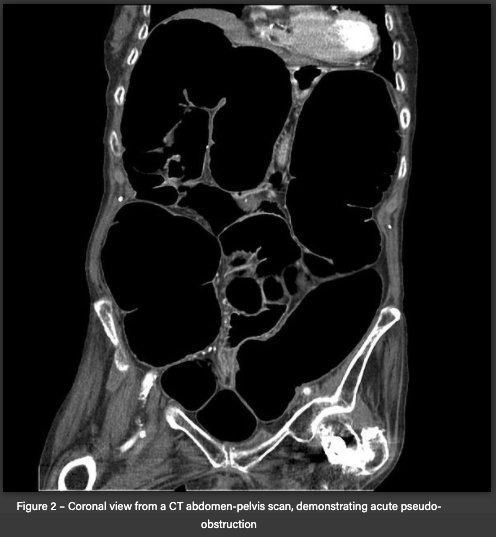

CT Abdo-pelvis with IV contrast

CT abdo-pelvis with IV contrast findings

Dilation of the colon + will be able to exclude mechanical obstruction

It can also show complications